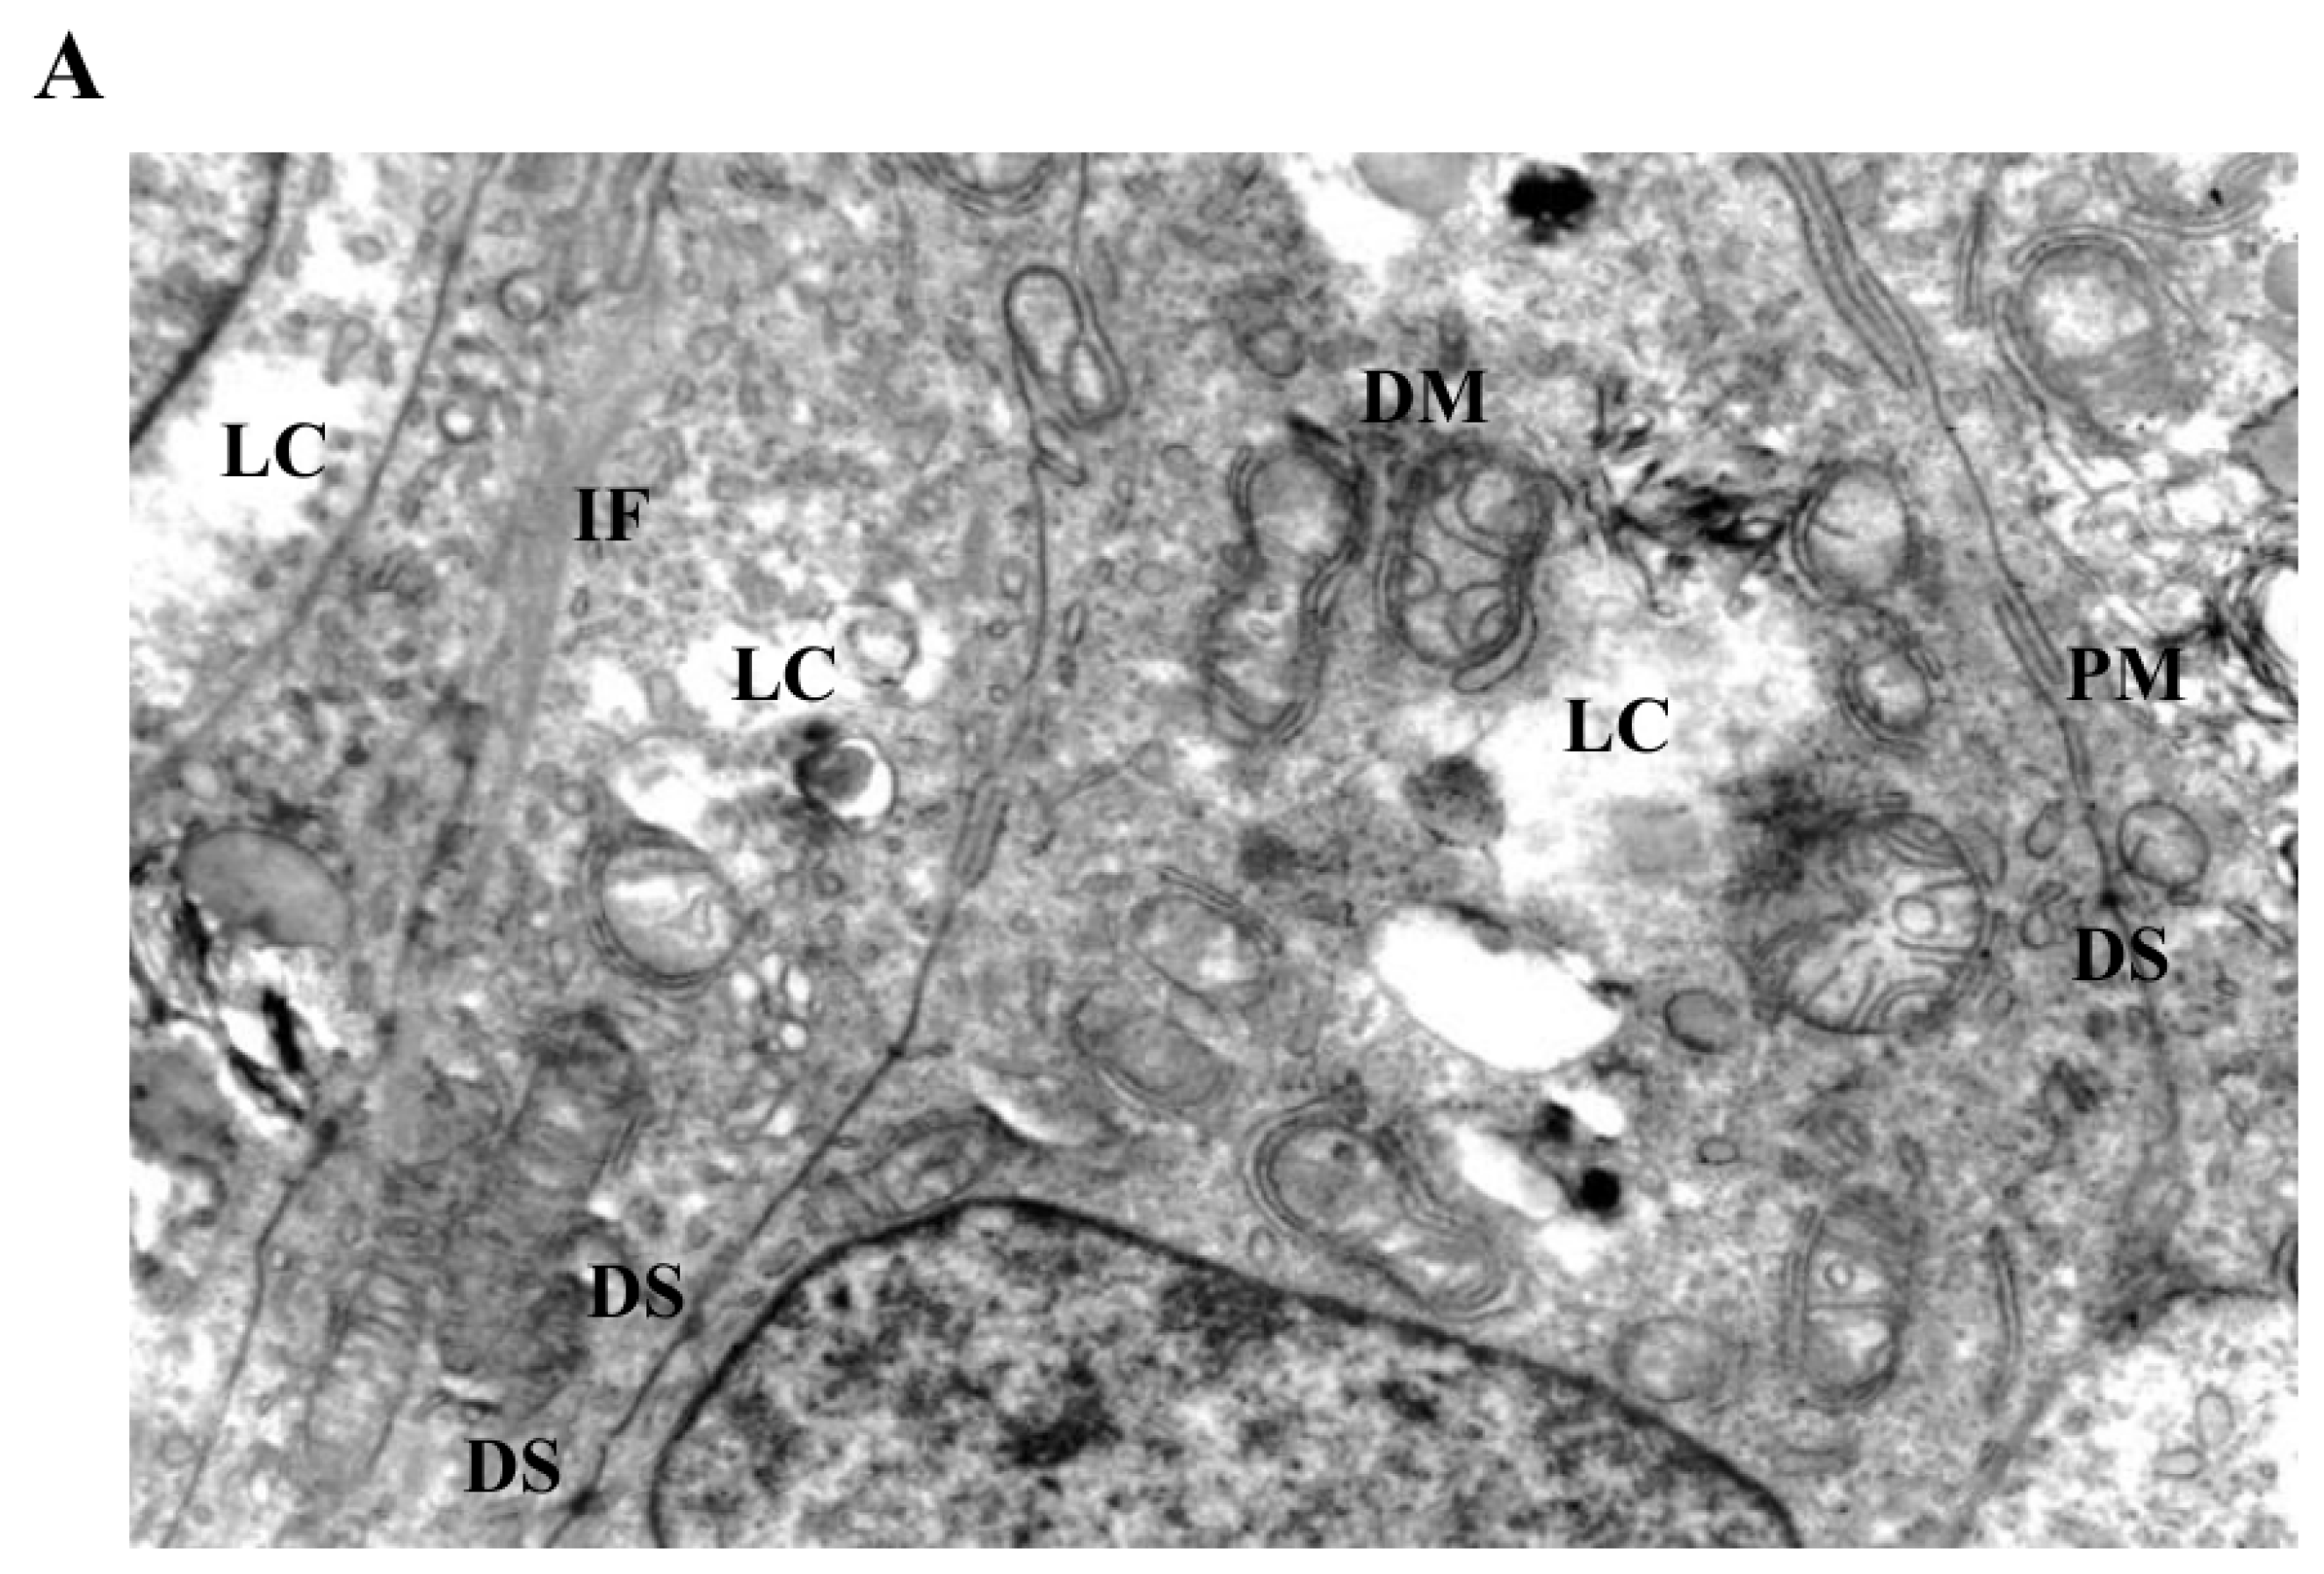

Figure 5.

Mitochondrial and cytoskeletal alterations following moderate LiCl exposure. (A) At 10 mM LiCl (24 h), mitochondria exhibit pronounced cristae loss, swelling, and frequent DM structures, accompanied by cytoplasmic lysis (LC) and marked IF accumulation. Desmosomal junctions (DS) remain preserved. (B) At 1 mM LiCl (72 h), mitochondria display early structural injury with initial cristae disruption and DM formation, consistent with early-stage mitochondrial stress responses. Abbreviations: M, mitochondrion; G, Golgi apparatus; PM, plasma membrane; DM, double membrane; IF, intermediate filament; DS, desmosome; LC, lytic cytoplasm. Scale bar: 500 nm.

At moderate LiCl concentration (10 mM), mitochondria exhibited more pronounced ultrastructural abnormalities, including cristae depletion, mitochondrial swelling, and frequent double-membrane structures (Figure 5A). Notably, these mitochondrial changes were accompanied by conspicuous accumulation and reorganization of intermediate filaments within the perimitochondrial cytoplasm. Despite these intracellular alterations, plasma membrane integrity and desmosomal junctions remained largely preserved. Prolonged exposure (72 h) further intensified mitochondrial disruption, intermediate filament accumulation, and the appearance of cytoplasmic lytic regions (Figure 6A).